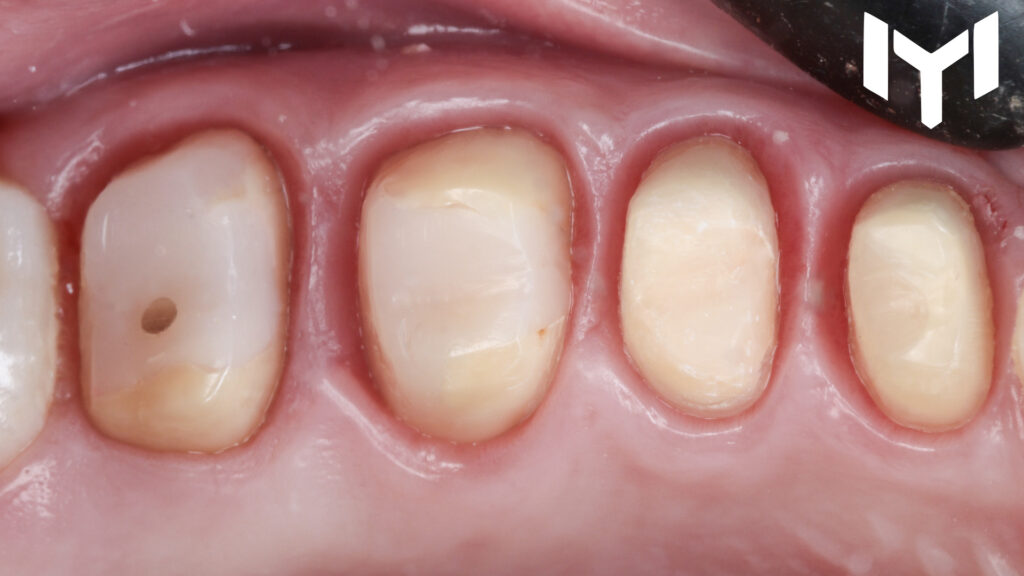

1- vertical preparation for the segment.

2. The Power of Temporization The “magic” happens during the healing phase. We placed high-quality provisional crowns for one month. This stage is crucial for:

• Guiding the gingival healing.

• Determining the ideal emergence profile.

• Ensuring the patient’s comfort and function before the final stage.